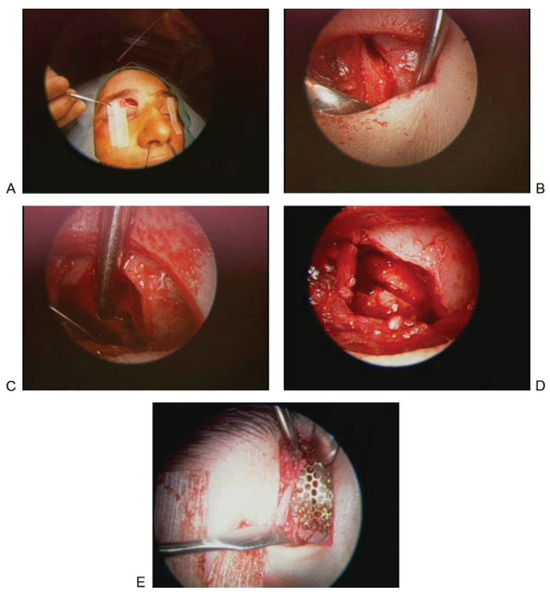

Figure 7.

(A) Axial computed tomographic showing fractures of the posterior aspect of the right frontal sinus and the intersinus septum. A frontal sinus trephination approach was used to manage this defect. (B) Intraoperative picture showing a drill being used to perform the trephination and expose the frontal sinus lumen. (C) Endoscopic view of the frontal sinus lumen through the trephination shows a small area of brain herniation (black arrow) into the frontal sinus through the posterior table defect. Endoscopic visualization also shows a patent frontal sinus outflow tract (white arrow). (D) After encephalocele cauterization, repair was performed using a bone graft and mucosal graft. Image shows mucosal graft in place (black arrow) and that the frontal sinus outflow tract remains patent (white arrow).

The patient in Figure 7A did not have an active CSF leak at the time of initial injury. Imaging showed a fracture along the posterior frontal sinus wall. In the absence of a CSF leak, no acute exploration or repair was performed. The patient presented 2 years later with an episode of meningitis. Imaging revealed an encephalocele at the site of the previous posterior wall injury. The defect was repaired by way of a frontal sinus trephination approach, as shown in Figure 7B–D. In this case, the defect was repaired using bone and mucosal grafts while maintaining a patent frontal sinus outflow tract.